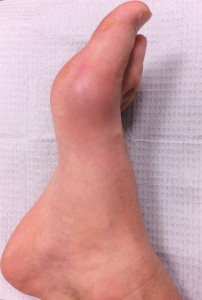

Ankle sprains are caused by a twisting injury or force on the ankle joint, often resulting in one or more ligaments of the ankle to be stretched or torn. Ankle injuries occur commonly while playing basketball, slipping on ice, and stepping incorrectly off of a curb. If not properly treated, ankle sprains can develop into chronic conditions. Symptoms include pain, swelling and bruising to the ankle and difficulty walking and participating in activities. X-rays are always taken in the office to rule out fracture and occasionally an MRI is ordered to evaluate the extent of injury to the ankle ligaments. Treatment includes rest, icing, stretching, bracing, MLS Laser therapy, physical therapy, and anti-inflammatories.